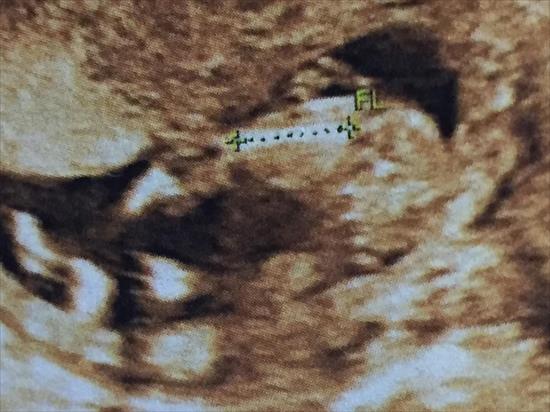

Attachment 32932What you thought? I think it is a girl...says my feeling :)

Please guesses